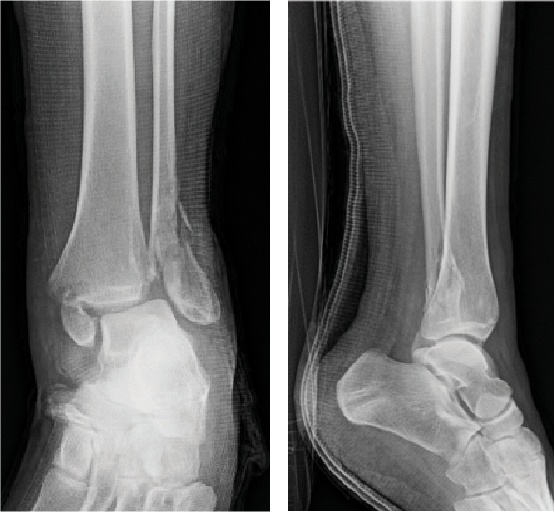

The patient is a 38-year-old opioid-naïve woman with no other significant past medical history who suffered a closed, left bimalleolar fracture with syndesmotic disruption in December 2017 when she slipped on ice and fell. She had no other injuries at the time. The patient went to the emergency department on the day of injury and was close reduced and splinted. She had open reduction internal fixation (ORIF) of the distal fibula with a lateral locking plate, cannulated screw fixation of the medial malleolar fracture and syndesmotic screw fixation eight days after injury when her swelling was improved.

The patient was non-weightbearing in a splint postoperatively. She received a popliteal and saphenous block by anesthesia preoperatively. We utilized our aforementioned protocol to manage her postoperative pain, again emphasizing scheduled non-narcotic medications and incorporating opioids only as necessary for breakthrough postoperative pain. At her first postoperative visit 13 days later, she reported adherence with her postoperative medication instructions. We had prescribed 30 tabs of oxycodone per our rearfoot and ankle protocol, and she used 18 tabs. The patient reported that she did not need oxycodone beyond postoperative day four. She went on to heal her fracture uneventfully and transitioned to pain-free weightbearing in regular shoe gear at 12 weeks post-op.